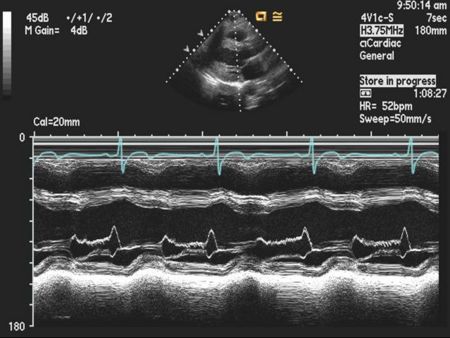

Mitral Valve M-mode Analysis

- Anterior leaflet with E/A appearance of diastology

- Decreased EF slope in MS

- Scalloping of leaflet tip in end systole in prolapse